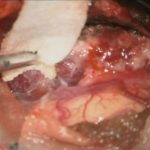

No.’25_60 摘出 前

No.’25_60  摘出 中